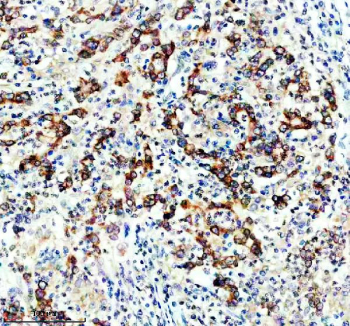

IHC staining of FFPE human stomach cancer tissue with DGAT1 antibody, HRP-secondary and DAB substrate. HIER: boil tissue sections in pH8 EDTA for 20 min and allow to cool before testing.